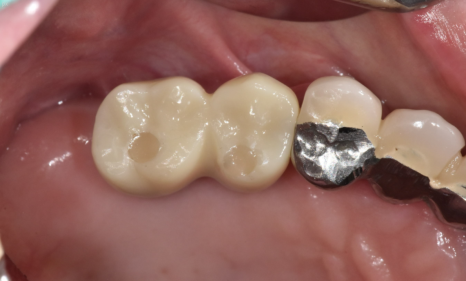

▼결과 공개▼

24.02.20

24년 2월에 치료를 끝내드렸습니다.

약 8개월정도 걸렸네요~

환자분께 지금 시작하셔도 내년에 끝난다

말씀드렸었는데

진짜죠~?

임플란트가 뼈와 붙은 시간이 필요해

한두달만에 치료가 완성되는 것이 아닙니다.

▼완성 사진▼